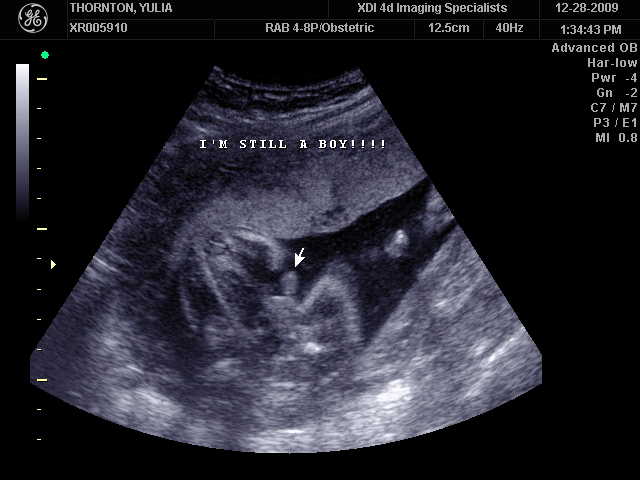

Ну ладно, тогда и я нашего писюна покажу  Надеюсь, Джеффри на меня не обидится Вот это в 23 недели: (там оборудование переключалось из режима 3Д в обычный 2Д)

А это в 30 недель

Sweetheart75 писал(а): Ну ладно, тогда и я нашего писюна покажу  Надеюсь, Джеффри на меня не обидится Вот это в 23 недели: (там оборудование переключалось из режима 3Д в обычный 2Д) Oоо, такое достоинство невозможно не заметить  А в 30 недель так вообще!